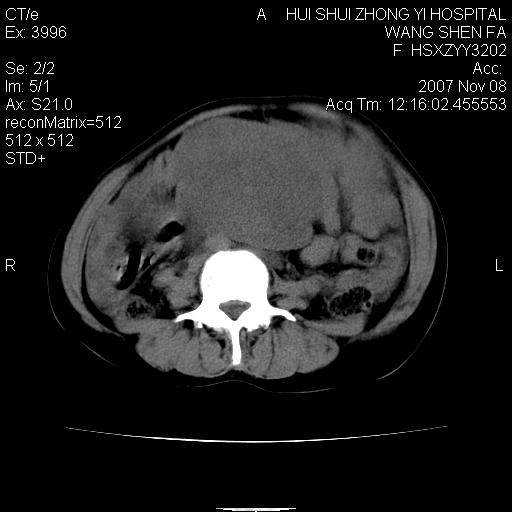

腹腔及盆腔内可见巨大软组织肿物影,内部密度欠均匀,边界尚清晰,周围组织受压移位明显,右侧输尿管受压明显,上端扩张肾盂轻度积水,病灶外形分叶明显,似多个肿物融合而成。考虑来源于间叶组织的恶性肿瘤可能性大

下腹部巨大软组织影,密度不均匀,并可见分隔,病灶边缘较清,肠管受压移位。子宫未显示。盆腔、双侧腹股沟未见明显肿大淋巴结。考虑:1.卵巢病变可能性大,囊腺癌>卵巢癌>囊腺瘤.2.多发性阔韧带子宫肌瘤待除外.

腹腔及盆腔内可见巨大软组织肿物影,内部密度欠均匀,边界尚清晰,周围组织受压移位明显,膀胱前上移位,右侧输尿管受压明显,上端扩张肾盂轻度积水。考虑:1卵巢病变可能性大,囊腺癌>卵巢癌>囊腺瘤.2 子宫病变,子宫肌瘤?

下腹部巨大软组织影,密度不均匀,并可见分隔,病灶边缘较清,肠管受压移位。病灶下部与子宫及附件关系密切。盆腔、双侧腹股沟未见明显肿大淋巴结。考虑:1.卵巢实质性肿瘤可能性大,卵巢癌>颗粒细胞>卵泡膜细胞瘤>纤维瘤.2.多发子宫肌瘤待除外.

下腹部巨大软组织影,密度不均匀,并可见分隔,病灶边缘较清,肠管受压移位。病灶下部与子宫及附件关系密切。盆腔、双侧腹股沟未见明显肿大淋巴结。考虑:1.卵巢实质性肿瘤可能性大,卵巢癌>颗粒细胞>卵泡膜细胞瘤>纤维瘤.2.多发子宫肌瘤待除外.3)间叶组织来源(脂肪肉瘤、平滑肌肉瘤)。